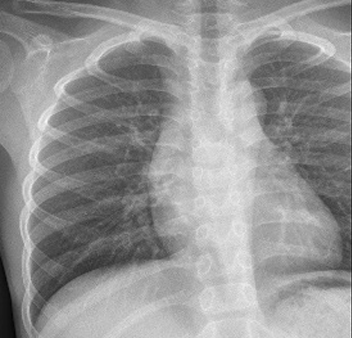

Table 6 Fused image output.

From: Multimodal medical image fusion combining saliency perception and generative adversarial network